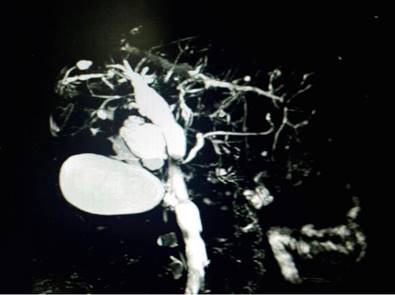

Se inició la pilocarpina con mejoría de los síntomas secos orales y tratamiento tópico ocular por parte de oftalmología. Desde hace 5 años fue remitida a hepatología por presencia de aspartato-aminotransferasa (AST) 77 mg/dL, alanina-aminotransferasa (ALT) 56 mg/dL, fosfatasa alcalina de 960 mg/dL, γ-glutamil transferasa (GGT): 632 mg/dL y bilirrubina total de 1,3 mg/dL. No tenía antecedente previo de consumo de medicamentos hepatotóxicos, ni historia de esteatosis hepática asociada a disfunción metabólica, ni de enfermedades cardiopulmonares crónicas. El perfil viral para virus de hepatitis B y hepatitis C fue negativo. Ulteriormente, los anticuerpos antimitocondriales (AMA) y la IgG4 fueron normales. No se realizaron anticuerpos anticitoplasma del neutrófilo (p-ANCA). Se realizaron estudios imagenológicos como la colangiorresonancia magnética (CRM) con hallazgos de pérdida del lóbulo caudado, con dilatación segmentaria de la vía biliar intrahepática con aspecto arrosariado asociado a dilatación del colédoco, hallazgos que fueron vistos en el contexto de una CEP (Figura 1).

Figura 1 CRM con hallazgos de patrón arrosariado de la vía biliar intrahepática y dilatación del colédoco. Imagen propiedad de los autores.